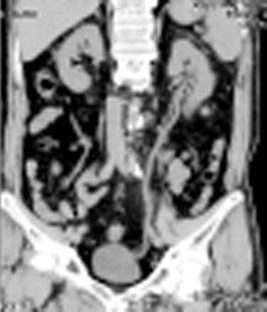

新病院移転と共に、80列マルチスライスCTを導入しました。以前の装置より広範囲をより速く撮影する事ができ、胸部撮影で約5秒、腹部撮影で約10秒の息止めにて撮影出来ます。また、最新の画像処理により以前より少ない被ばく線量にて検査を受ける事が出来るようになりました。

細かいスライスで撮影するため小さな結石でも容易に発見ができ、正確な位置情報を診断する事が出来ます。

従来の輪切りの画像だけではなく、さまざまな方向からの断面像や画像解析装置による診断に有効な3D(立体)表示をして臓器(主に腎臓・前立腺・膀胱)や病巣の大きさ・形状を把握する事が出来ます。造影剤を使用しながら撮影する事により、より鮮明な画像が得られます。